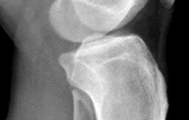

A 53-year-old man sustains a fall while skiing. He experiences immediate pain and deformity in his lower leg just above his ski boot top. Radiographs of his left lower leg are shown in Figures 1 and

After discussing operative management with the patient, you choose to proceed with an intramedullary nail. Where should blocking screws be placed to prevent the characteristic deformity of this fracture?

The patient has sustained a proximal third tibia and fibula fracture, sometimes referred to as a "boot top" fracture when sustained while alpine skiing. These fractures frequently fall into apex anterior and valgus

angulation as shown in the radiographs. Great care needs to be taken during intramedullary nailing to avoid fixing the fracture in a malreduced position. The use of Poller blocking screws in the posterior and lateral aspects of the proximal fragment can help to avoid this complication (posterior screw prevents flexion deformity while lateral screw prevents valgus deformity). Additional technical pearls include starting with a more lateral entry point for the guidewire, placing a provisional unicortical plate prior to nailing to maintain the reduction, or using a suprapatellar entry nail to allow for fixation with the knee in _a semi-extended position._